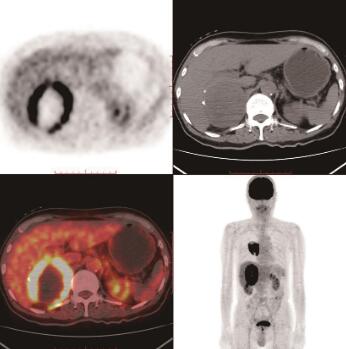

图2 右肾上腺癌

18F-FDG PET/CT横断位示右肾上腺区巨大稍低密度肿块影,边缘见钙化灶,与右肾及肝脏分界不清,代谢异常增高,SUVmax为18.9

右肺下叶背段见一软组织肿块影,大小约6.2cm×5.6cm×8.5cm,上份见钙化点,内后缘与胸壁相连,邻近胸膜增厚,肿块放射性不均匀增高,SUVmax约19.5,其内见大片液化坏死区呈放射性缺损区(图1)。右肾上腺区见一巨大稍低密度肿块影,大小约8.0cm×6.6cm×11.1cm,边缘见钙化灶,与右肾及肝脏分界不清,肿块放射性不均匀增高,SUVmax约18.9(图2)。